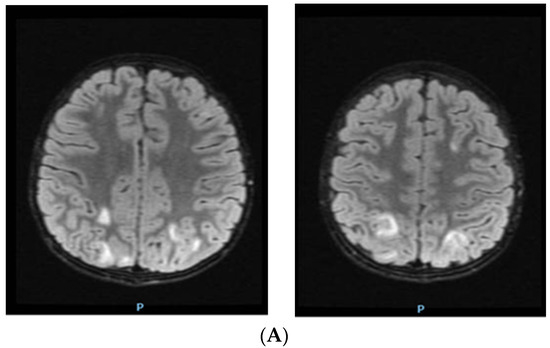

2. Case Report